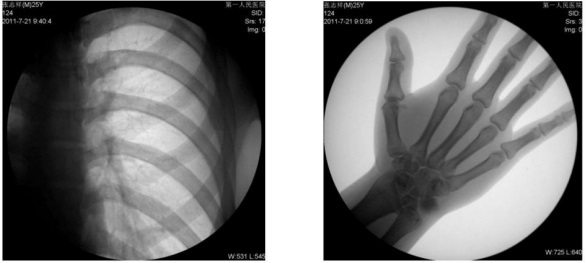

1、數(shù)字化透視:適用于全身各部位透視(如胸透、腹透等)。

動態(tài)采集速度≥25 幀/秒,主要應(yīng)用于臨床各科室,尤其是體檢科、內(nèi)科、外科、骨科、創(chuàng)傷科、急診科等。

1) 胸部檢查:能實現(xiàn)全胸透視動態(tài)觀察,對于需要在透視下動態(tài)觀察的病變,如肺部腫瘤、氣管異物等可進行實時點片。胸部透視是體檢中的常規(guī)檢查項目,臨床意義在于檢查有無肺癌, 特別是早期肺癌。使用胃腸機可通過胸部透視雙肺,縱膈有無病變,以確定病變部位的部位、大小、密度,與周邊組織關(guān)系,常見的疾病,如肺炎、肺結(jié)核等。胃腸機可以從各種角度動態(tài)詳細(xì)觀察肺、心臟或其他胸部的病變,對病變的情況可以有個比較全面地了解。